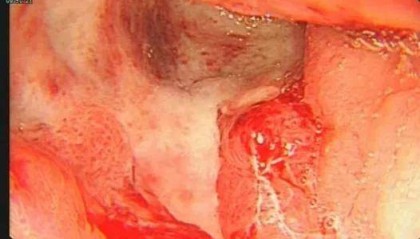

24岁女演员确诊“癌王”,崩溃痛悔:大家别像我这样

今年24岁的小雯(化名),长得清秀漂亮,从小就对表演充满热情,常常对着镜子模仿电视剧中的角色。上大学...